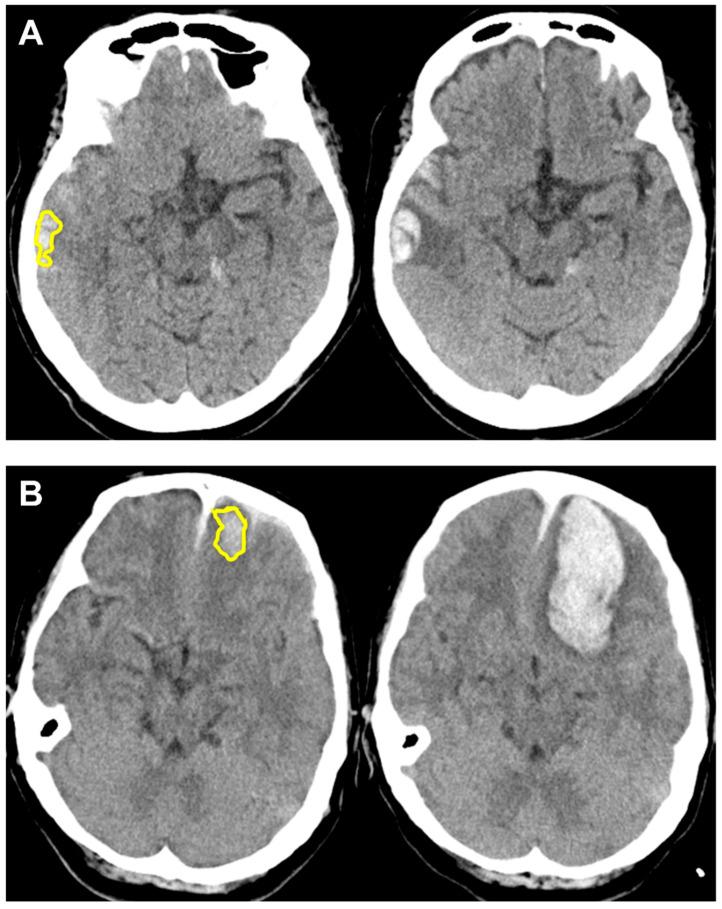

(1) Background: Radiomics analysis of spontaneous intracerebral hemorrhages on computed tomography (CT) images has been proven effective in predicting hematoma expansion and poor neurologic outcome. In contrast, there is limited evidence on its predictive abilities for traumatic intraparenchymal hemorrhage (IPH). (2) Methods: A retrospective analysis of 107 traumatic IPH patients was conducted. Among them, 45 patients (42.1%) showed hemorrhagic progression of contusion (HPC) and 51 patients (47.7%) had poor neurological outcome. The IPH on the initial CT was manually segmented for radiomics analysis. After feature extraction, selection and repeatability evaluation, several machine learning algorithms were used to derive radiomics scores (R-scores) for the prediction of HPC and poor neurologic outcome. (3) Results: The AUCs for R-scores alone to predict HPC and poor neurologic outcome were 0.76 and 0.81, respectively. Clinical parameters were used to build comparison models. For HPC prediction, variables including age, multiple IPH, subdural hemorrhage, Injury Severity Score (ISS), international normalized ratio (INR) and IPH volume taken together yielded an AUC of 0.74, which was significantly ( = 0.022) increased to 0.83 after incorporation of the R-score in a combined model. For poor neurologic outcome prediction, clinical variables of age, Glasgow Coma Scale, ISS, INR and IPH volume showed high predictability with an AUC of 0.92, and further incorporation of the R-score did not improve the AUC. (4) Conclusion: The results suggest that radiomics analysis of IPH lesions on initial CT images has the potential to predict HPC and poor neurologic outcome in traumatic IPH patients. The clinical and R-score combined model further improves the performance of HPC prediction.

(1)背景:计算机断层扫描(CT)图像上自发性脑出血的放射组学分析已被证明在预测血肿扩大和不良神经结局方面有效。相比之下,关于其对创伤性脑实质内出血(IPH)预测能力的证据有限。(2)方法:对107例创伤性IPH患者进行回顾性分析。其中,45例患者(42.1%)出现挫伤性出血进展(HPC),51例患者(47.7%)神经功能结局不良。对初始CT上的IPH进行手动分割以进行放射组学分析。在特征提取、选择和重复性评估后,使用几种机器学习算法得出放射组学评分(R评分),以预测HPC和不良神经结局。(3)结果:单独的R评分预测HPC和不良神经结局的AUC分别为0.76和0.81。使用临床参数建立比较模型。对于HPC预测,包括年龄、多发IPH、硬膜下出血、损伤严重程度评分(ISS)、国际标准化比值(INR)和IPH体积的变量综合起来的AUC为0.74,在联合模型中纳入R评分后显著(P = 0.022)提高到0.83。对于不良神经结局预测,年龄、格拉斯哥昏迷量表、ISS、INR和IPH体积的临床变量显示出较高的预测性,AUC为0.92,进一步纳入R评分并未提高AUC。(4)结论:结果表明,初始CT图像上IPH病变的放射组学分析有可能预测创伤性IPH患者的HPC和不良神经结局。临床和R评分联合模型进一步提高了HPC预测的性能。